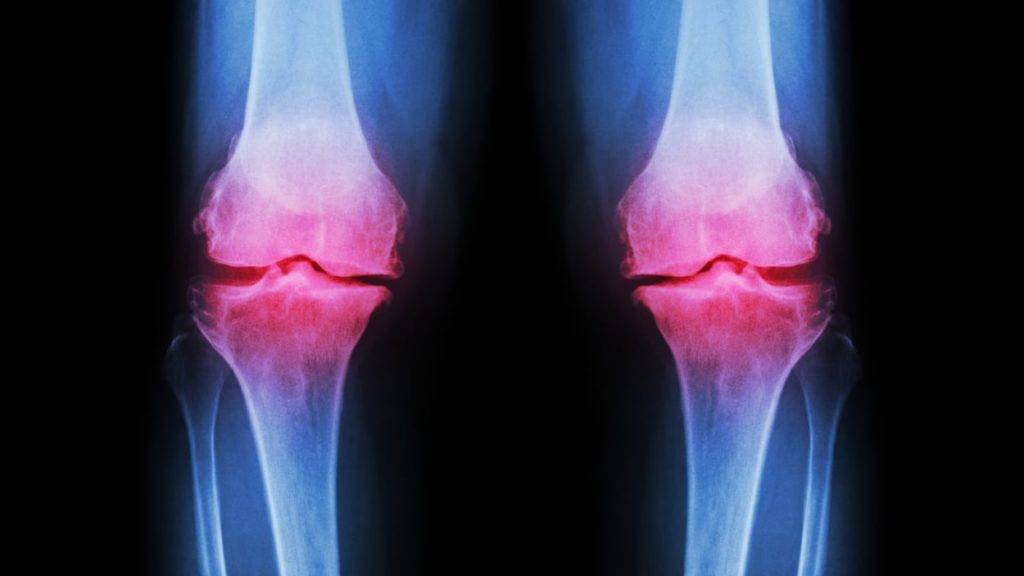

Ревматоидный артрит

Ревматоидный артрит является системным аутоиммунным заболеванием. Он поражает суставы и соединительные ткани по эрозивно-деструктивному типу. Этот вид артрита может затрагивать даже внутренние органы. Большинство его случаев приводит к тому, что пациенты становятся инвалидами. Как правило, ревматоидный артрит появляется в 40-50 лет, причем чаще всего у женщин.

При ревматоидном артрите происходит симметричное поражение суставов, которые воспаляются и отекают. Боль исчезает во второй половине дня, но усиливается ночью. Сначала артрит поражает мелкие суставы, а затем уже и крупные. Кроме того, в месте сгиба суставов образуются небольшие плотные образования. В течение всего заболевания пациент испытывает общее недомогание, слабость и ухудшение аппетита. При обострении артрита повышается температура тела. Также могут наблюдаться следующие симптомы:

При остеоартрите могут поражаться суставы конечностей и позвоночный столб. Болезнь протекает медленно. Сначала появляется хруст и отечность в месте, где началось воспаление. Постепенное разрушение хрящевой ткани приводит к усилению болей, деформации сустава и образованию костных наростов. Опасность остеоартрита в том, что хрящи и кости, которые подверглись деструкции, уже не могут восстановиться самостоятельно.